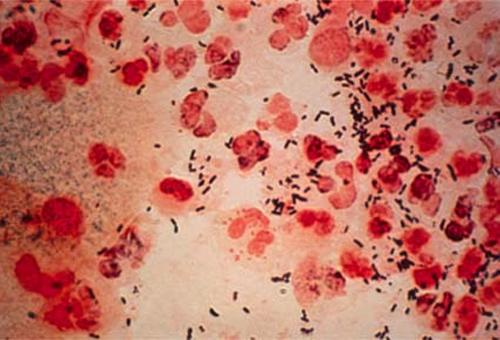

Ảnh lậu cầu dưới kính hiển vi

Bệnh lậu cầu được phát hiện lần đầu tiên vào năm 1979 và không lâu trở thành đại dịch, tạo ra mối nguy hiểm rất lớn đe dọa đến sức khỏe cộng đồng. Lậu cầu có thể xuất hiện ở bất cứ đối tượng này, ngay cả trẻ sơ sinh cũng có nguy cơ nhiễm mầm bệnh từ mẹ. Khuẩn Neisseria Gonorrhoeae được xác định là thủ phạm gây ra bệnh lý này.